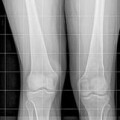

Fig. 4

Anteroposterior pre-operative view right foot radiograph of a short fourth metatarsal. Note the abnormal short fourth metatarsal length while the length of the distal, middle, and proximal phalanges of fourth toe are also abnormally short compared to the fifth toe. This indicates that the radiographic projection of a dorsally extended toe distorts the measurement of the true phalangeal length, which must be taken into consideration (Reprinted with permission from the Rubin Institute for Advanced Orthopedics, Sinai Hospital of Baltimore)